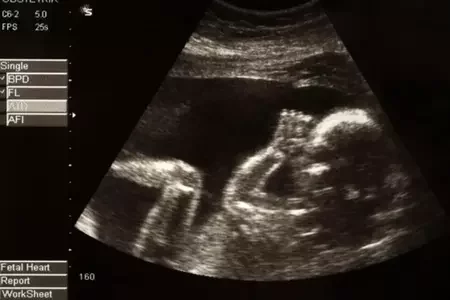

Скандал в США: главная проабортная организация торгует детскими органами 56